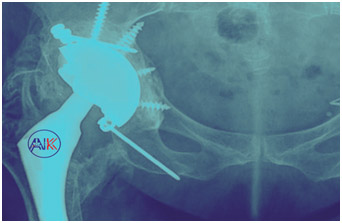

Several tailored approaches to hip replacement surgery are available to meet your specific needs. Personalised Total Hip Replacement Surgery customises the procedure to your unique anatomy and lifestyle and in cases where a previous hip replacement has failed or worn out, Revision Hip Replacement (Arthroplasty) may be necessary. This complex procedure involves removing and replacing the old prosthesis with new components, addressing any issues that have arisen since the original surgery. Revision surgery requires careful planning and advanced surgical expertise to effectively restore function and relieve pain.